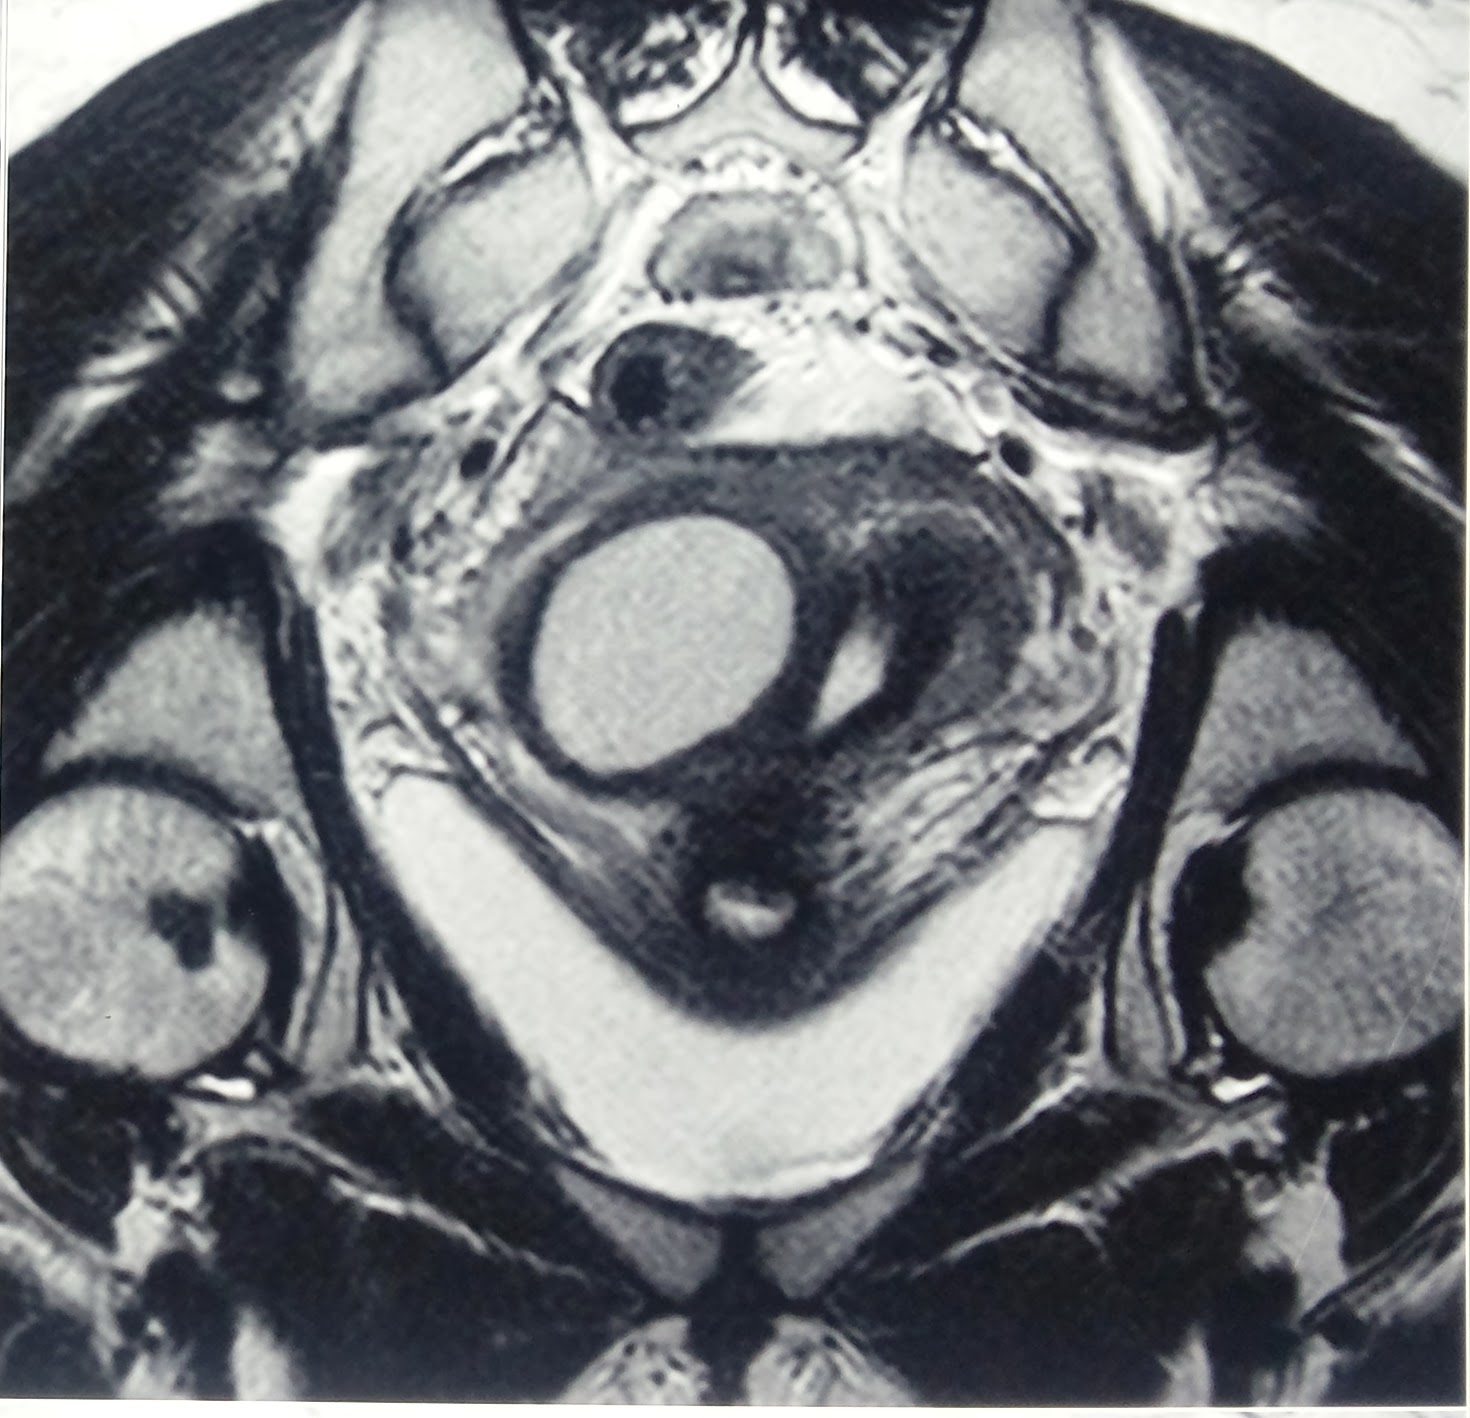

From www.researchgate.net

Cross sections of bovine uterine horns from (a) prooestrus and (b Single Horn Uterus A unicornuate uterus is a genetic condition that causes only half of your uterus to form. This is why the condition is. The unicornuate uterus, characterized by a single uterine horn, poses unique challenges due to its asymmetry and. As a result, you may have a. A unicornuate uterus or unicornis unicollis is a type of müllerian duct anomaly (class. Single Horn Uterus.